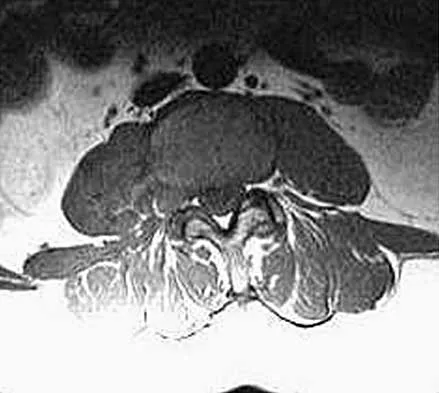

Master AAOS & ABOS boards with high-yield practice MCQs for Set 4, focusing on cervical & thoracolumbar verte…

Master AAOS, ABOS & OITE boards with Set 3 spine surgery MCQs. Covers degenerative spinal conditions, vertebr…

Master AAOS & ABOS boards with high-yield MCQs for Set 2. Review crucial topics like lumbar stenosis, cervica…

Master AAOS & ABOS Spine Surgery boards with Set 1 practice MCQs. Covers degenerative spine conditions, traum…